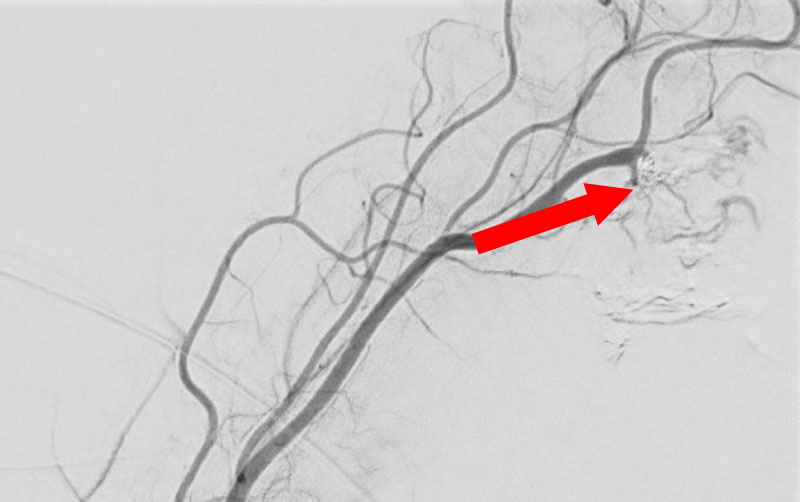

No.1585 手術前

No.1585 手術中

No.1585 手術後